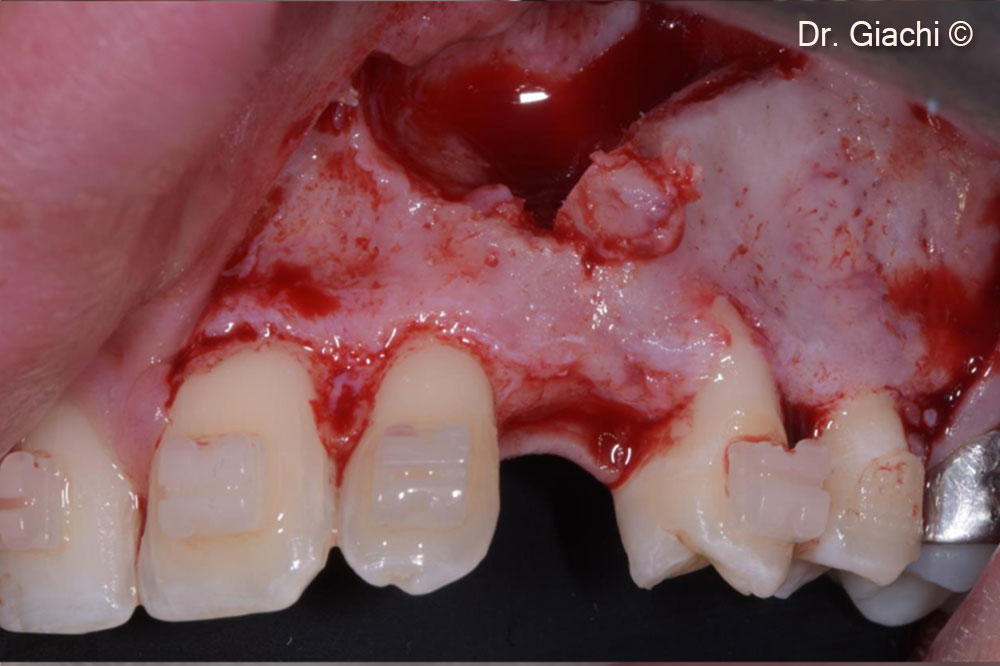

Một bệnh nhân nam (16 tuổi) có răng nanh trên không thể phục hồi bằng phương pháp chỉnh nha truyền thống.

Vật liệu sinh học đã qua sử dụng

Gel-OS